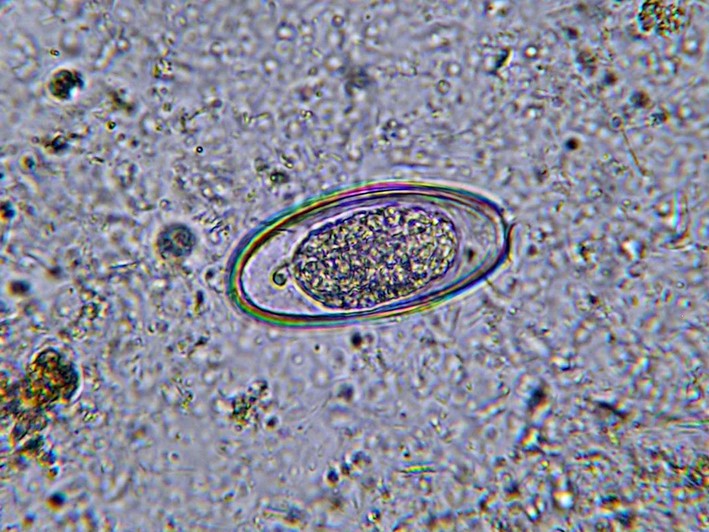

Микроскопический размер яиц позволяет рассмотреть их только под сильным увеличением. Как выглядят яйца остриц под микроскопом? Фото ниже даст ответ на этот вопрос. Лаборант, исследуя биоматериал, наблюдает следующую картину. Форма яйца овальная, причем одна сторона более выпуклая. Внутри находится вытянутая личинка. Оболочка яйца состоит из двух контуров и полностью бесцветна.

Увидеть яйца паразитов невооруженным глазом в кале невозможно, они слишком малы, заметны исключительно под микроскопом. Яйца паразитов имеют овальную форму, выпуклую с одной стороны. После освобождения от защитной оболочки личинки начинают перемещаться, закрепляются на стенках толстой, слепой кишки.